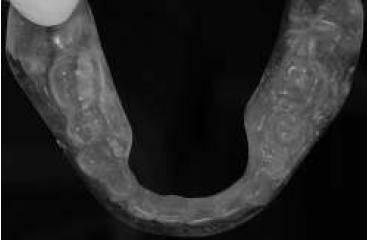

Para la rehabilitación inferior se realizó el duplicado del enfilado dentario en acrílico transparente mediante impresión en 2 pasos con silicona pesada de adición, con ello se obtuvo una guía multifuncional11 (figs. 3 y 4). Esta guía tuvo como objetivos: a) servir de referencia en el momento de la instalación de los implantes; b) utilizarse como cubeta en el momento de la toma de impresión a boca cerrada; y c) registrar y transferir las relaciones intermaxilares. Esta guía fue probada y esterilizada antes de la cirugía.